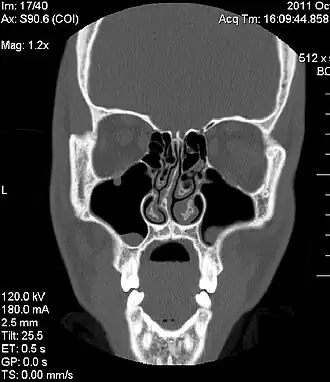

Изображение компьютерной томографии, показывающее отклонение носовой перегородки

Искривле́ние носово́й перегоро́дки — отклонение перегородки в обе или одну сторону от средней линии. Проявляется затруднением или отсутствием носового дыхания через один или оба носовых хода. Затрудняя отток секрета из придаточных пазух, повышает склонность к возникновению воспалительных и аллергических заболеваний органов дыхания, в том числе насморка, аллергического ринита, вазомоторного ринита, гайморита, синусита, тонзиллита.